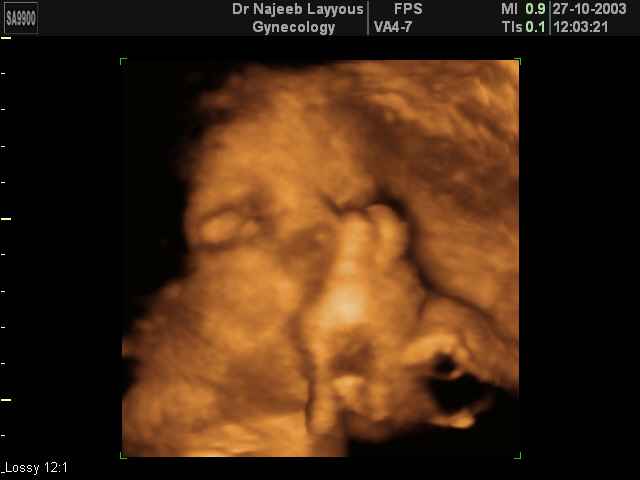

- Fetal Behavior Ultrasound Photos

Ultrasound Photos in 3D showing Fetal Behavior Inside the uterus | Dr N Layyous